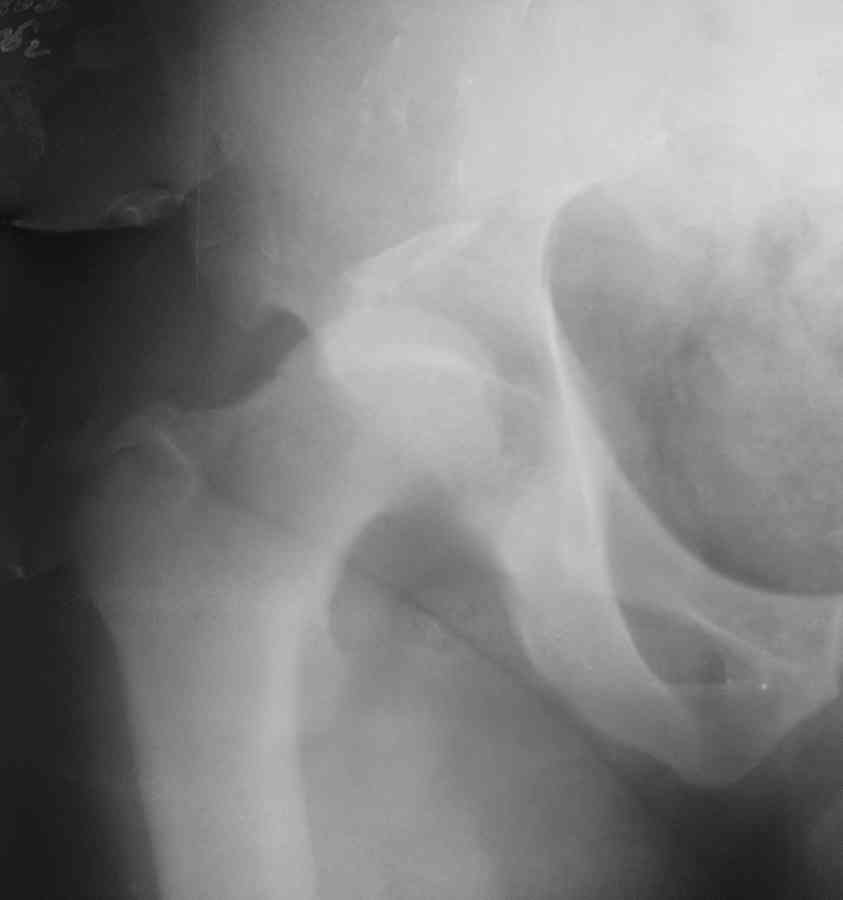

К нам обратился житель Казахстана с застарелым вывихом бедра. Травма год назад, вместо синтеза заднего края казахскими умельцами установлена клинковая пластина, через 6 мес удалена. Больной ходит с тростью,сгибание в т-б 90, разгибание 170, укорочение 5 см, боли не выражены, анальгетиками не пользуется. Настроен на эндопротезирование в клинике, где есть опыт подобных операций (возможно за рубежом).Наш план: аппарат таз-бедро, постепенное низведение бедра, "октопус" с пластикой. Но с такими большими дефектами мы не сталкивались.Есть вариант сначала аппарат, затем реконструкция впадины, протез обычный через 4-6 мес.Есть мнение не восстанавливать длину. Будем признательны за полезные советы. Было бы интересно посмотреть пример.

Кстати, судя по рентгенограммам и КТ истинная разница в длине ног не столь велика, укорочение, главным образом, за счет контрактур.